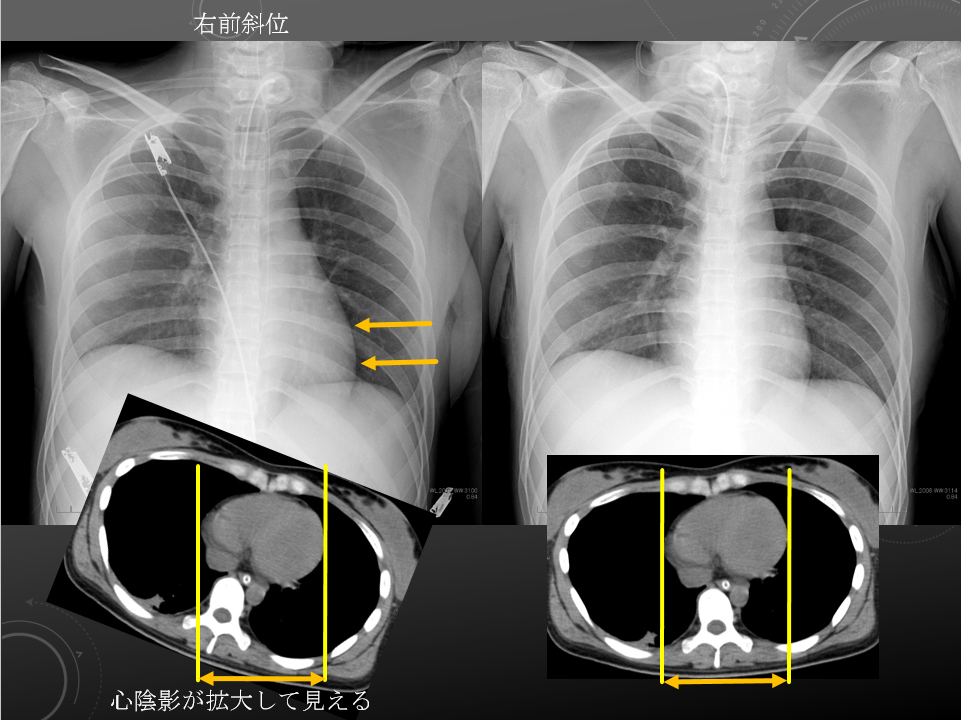

右前斜位